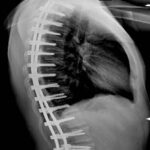

- Orientamento degli ultimi anni: solo artrodesi posteriore con sintesi peduncolare e osteotomie di Ponte

- Nostra strategia degli ultimi 10 anni, dopo la fase della chirurgia combinata: solo tempo posteriore, alta densità di viti peduncolari (oltre 90%) e osteotomie di Ponte.

- Inizialmente Montaggi Ibridi Unicini e Viti

- Successivamente montaggi Peduncolari